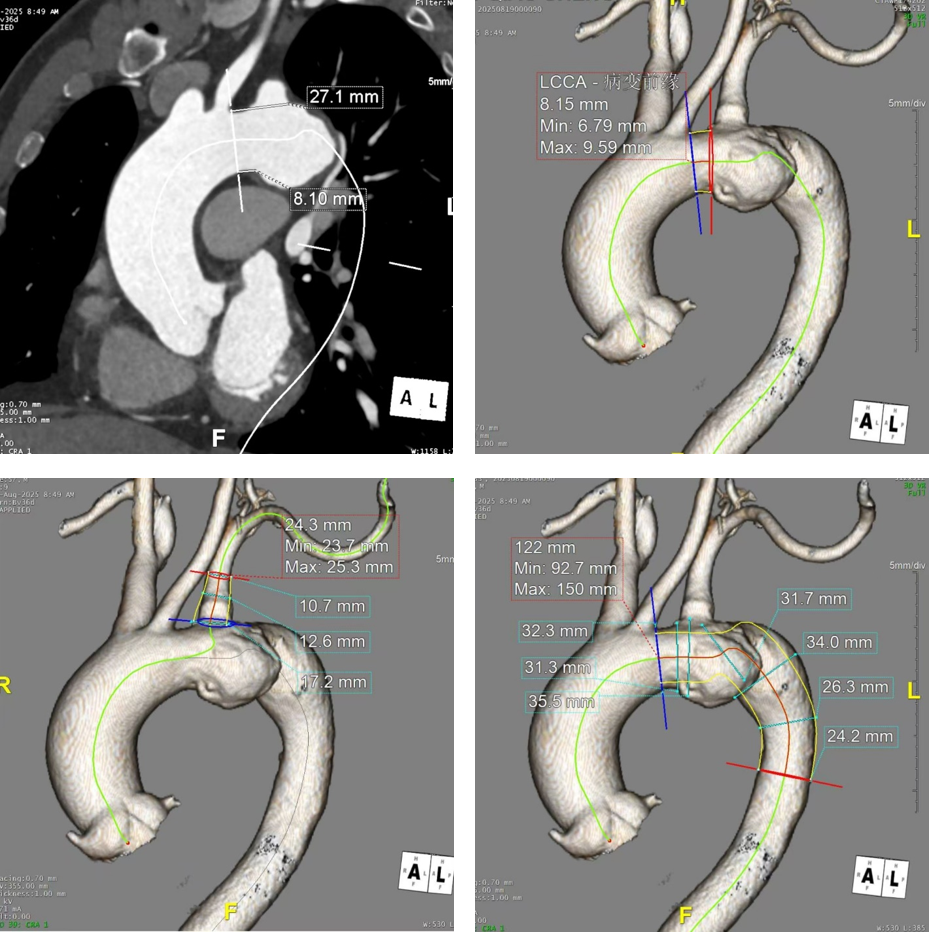

CASE 1:胸主动脉瘤累及左锁骨下动脉前缘

患者资料:男性,57岁,因“胸闷、胸痛5月余,加重1周”入院。CTA提示主动脉弓下缘动脉瘤伴局限性穿透性溃疡,病变紧贴左锁骨下动脉前缘,但左颈总动脉后缘至左锁骨下动脉后缘距离足够(锚定区充足)。

手术过程

经股动脉入路,将主体支架输送至降主动脉后解缠绕,精准定位至左锁骨下动脉后缘。

释放主体支架,造影确认内嵌孔道开口对准左锁骨下动脉。

沿内嵌孔道导入分支支架,球囊扩张分支连接处及远端,最终造影显示动脉瘤隔绝良好,左锁骨下动脉血流通畅。

体会

该病例锚定区测量充分,但术中释放主体支架时需注意:由于TBE支架采用拉线式中部优先释放,若释放后支架略有后移,可能影响近端锚定。本例释放后支架轻微后退,恰好卡在瘤颈位置,但令人欣慰的是造影未见任何内漏,证实其近端密封性能优越。这也提示术者在释放过程中应适当前推补偿后移量,以获得最佳定位。